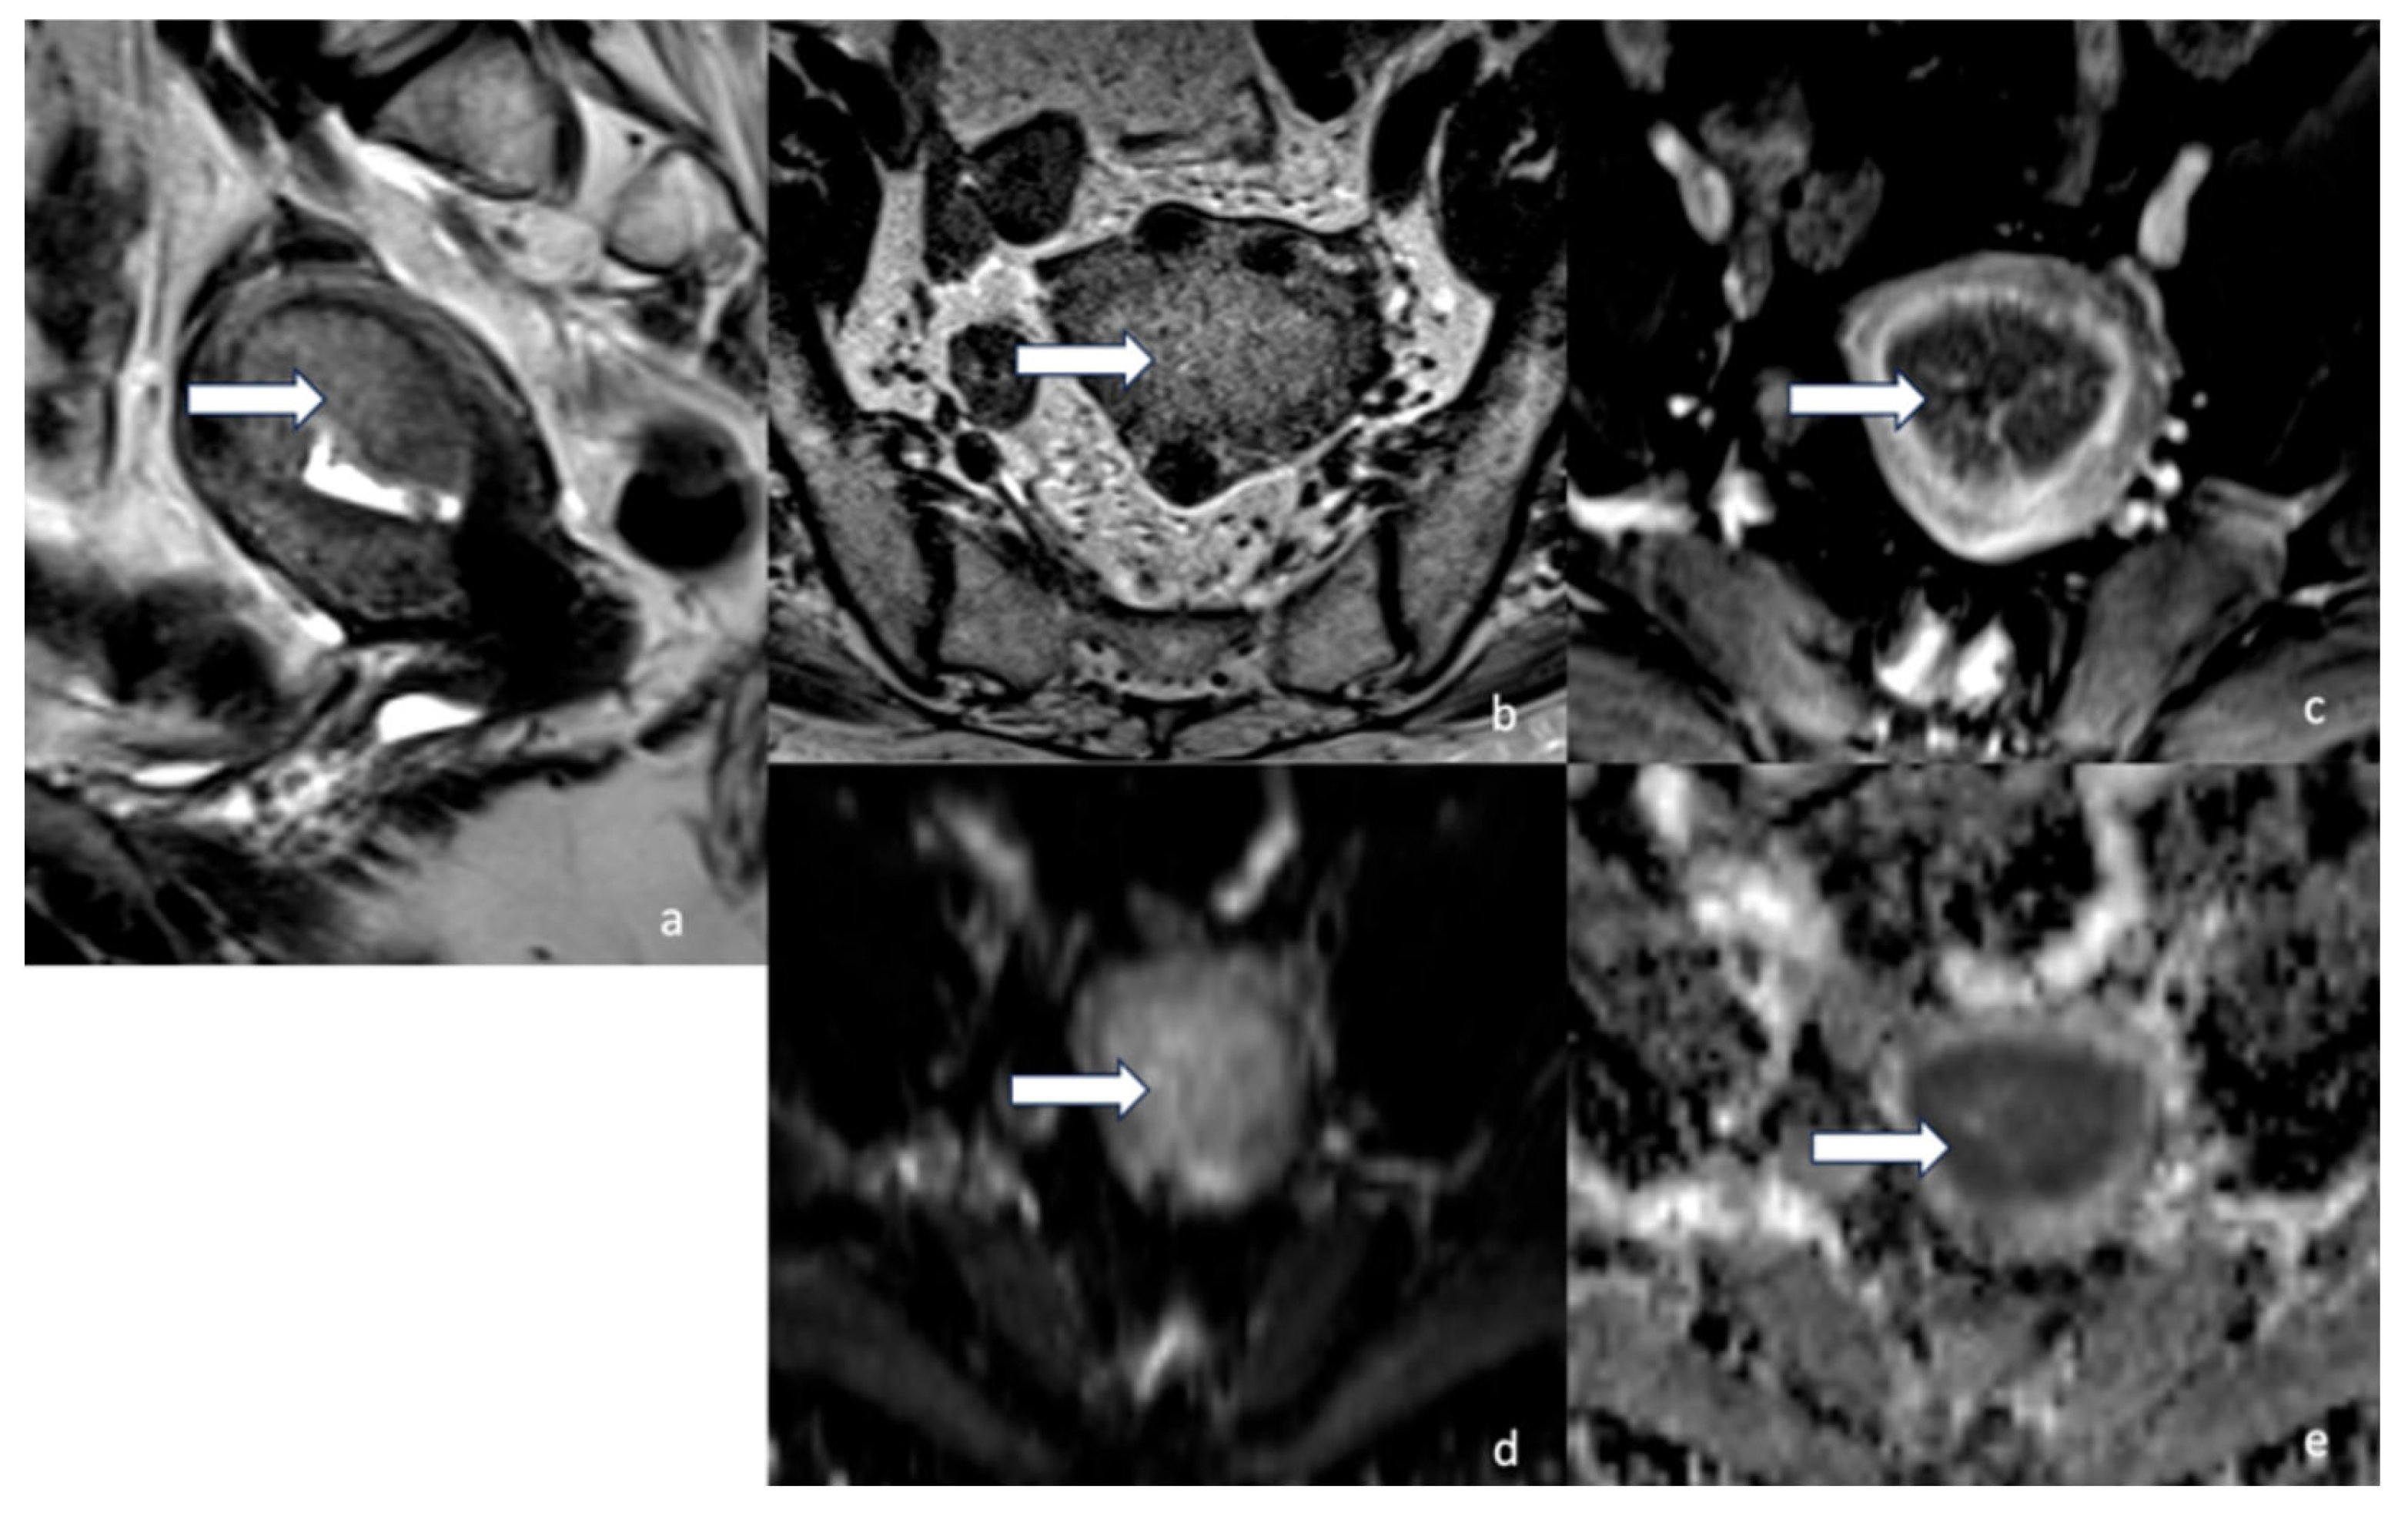

5.3. Magnetic Resonance Imaging (MRI)

- Maheshwari, E.; Nougaret, S.; Stein, E.B.; Rauch, G.M.; Hwang, K.-P.; Stafford, R.J.; Klopp, A.H.; Soliman, P.T.; Maturen, K.E.; Rockall, A.G.; et al. Update on MRI in Evaluation and Treatment of Endometrial Cancer. RadioGraphics 2022, 42, 2112–2130. [Google Scholar] [CrossRef] [PubMed]

- Neves, T.R.; Correia, M.T.; Serrado, M.A.; Horta, M.; Caetano, A.P.; Cunha, T.M. Staging of Endometrial Cancer Using Fusion T2-Weighted Images with Diffusion-Weighted Images: A Way to Avoid Gadolinium? Cancers 2022, 14, 384. [Google Scholar] [CrossRef] [PubMed]

- Nougaret, S.; Horta, M.; Sala, E.; Lakhman, Y.; Thomassin-Naggara, I.; Kido, A.; Masselli, G.; Bharwani, N.; Sadowski, E.; Ertmer, A.; et al. Endometrial Cancer MRI staging: Updated Guidelines of the European Society of Urogenital Radiology. Eur. Radiol. 2019, 29, 792–805. [Google Scholar] [CrossRef]